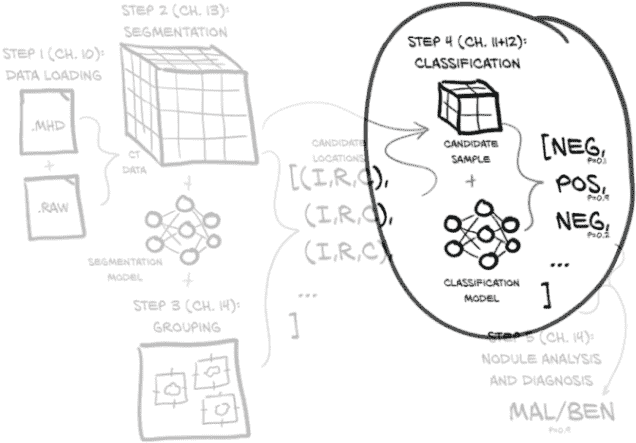

这意味着我们仍然专注于与第十一章相同的图 12.1 的同一部分。但现在我们正在努力使我们的分类模型工作良好而不是只是工作。本章重点讨论如何衡量、量化、表达,然后改进我们的模型执行工作的能力。

图 12.1 我们的端到端肺癌检测项目,重点放在本章的主题上:第 4 步,分类